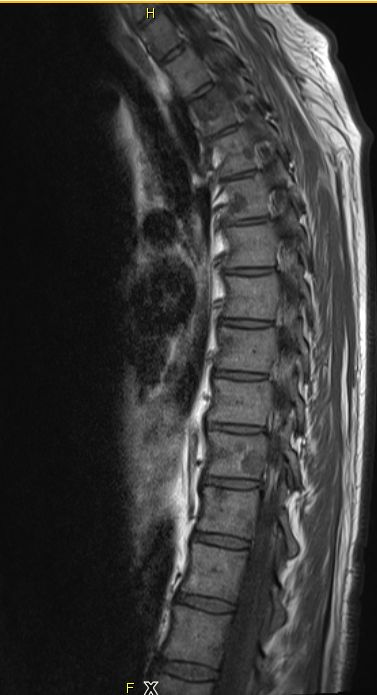

| Knochen - Metastasierung | ![]() |

![]() |